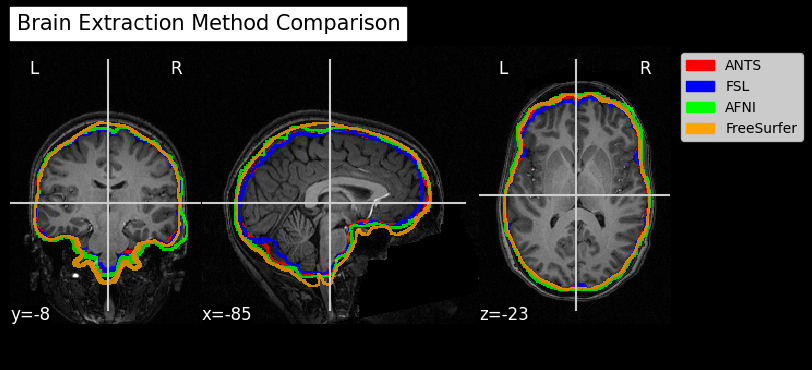

Since fMRI studies focus on brain tissue, our first step is to remove the skull and non-brain areas from the image.

In order to analyze fMRI data, you will need to load an fMRI analysis package. In this example we will use the following packages and algorithms to skull-strip the anatomical image:

Advanced Normalization Tools (ANTs): antsBrainExtraction.sh

Analysis of Functional NeuroImages (AFNI): 3dSkullStrip

FreeSurfer: SynthStrip

FSL (FMRIB Software Library, created by the University of Oxford): BET - Brain Extraction Tool